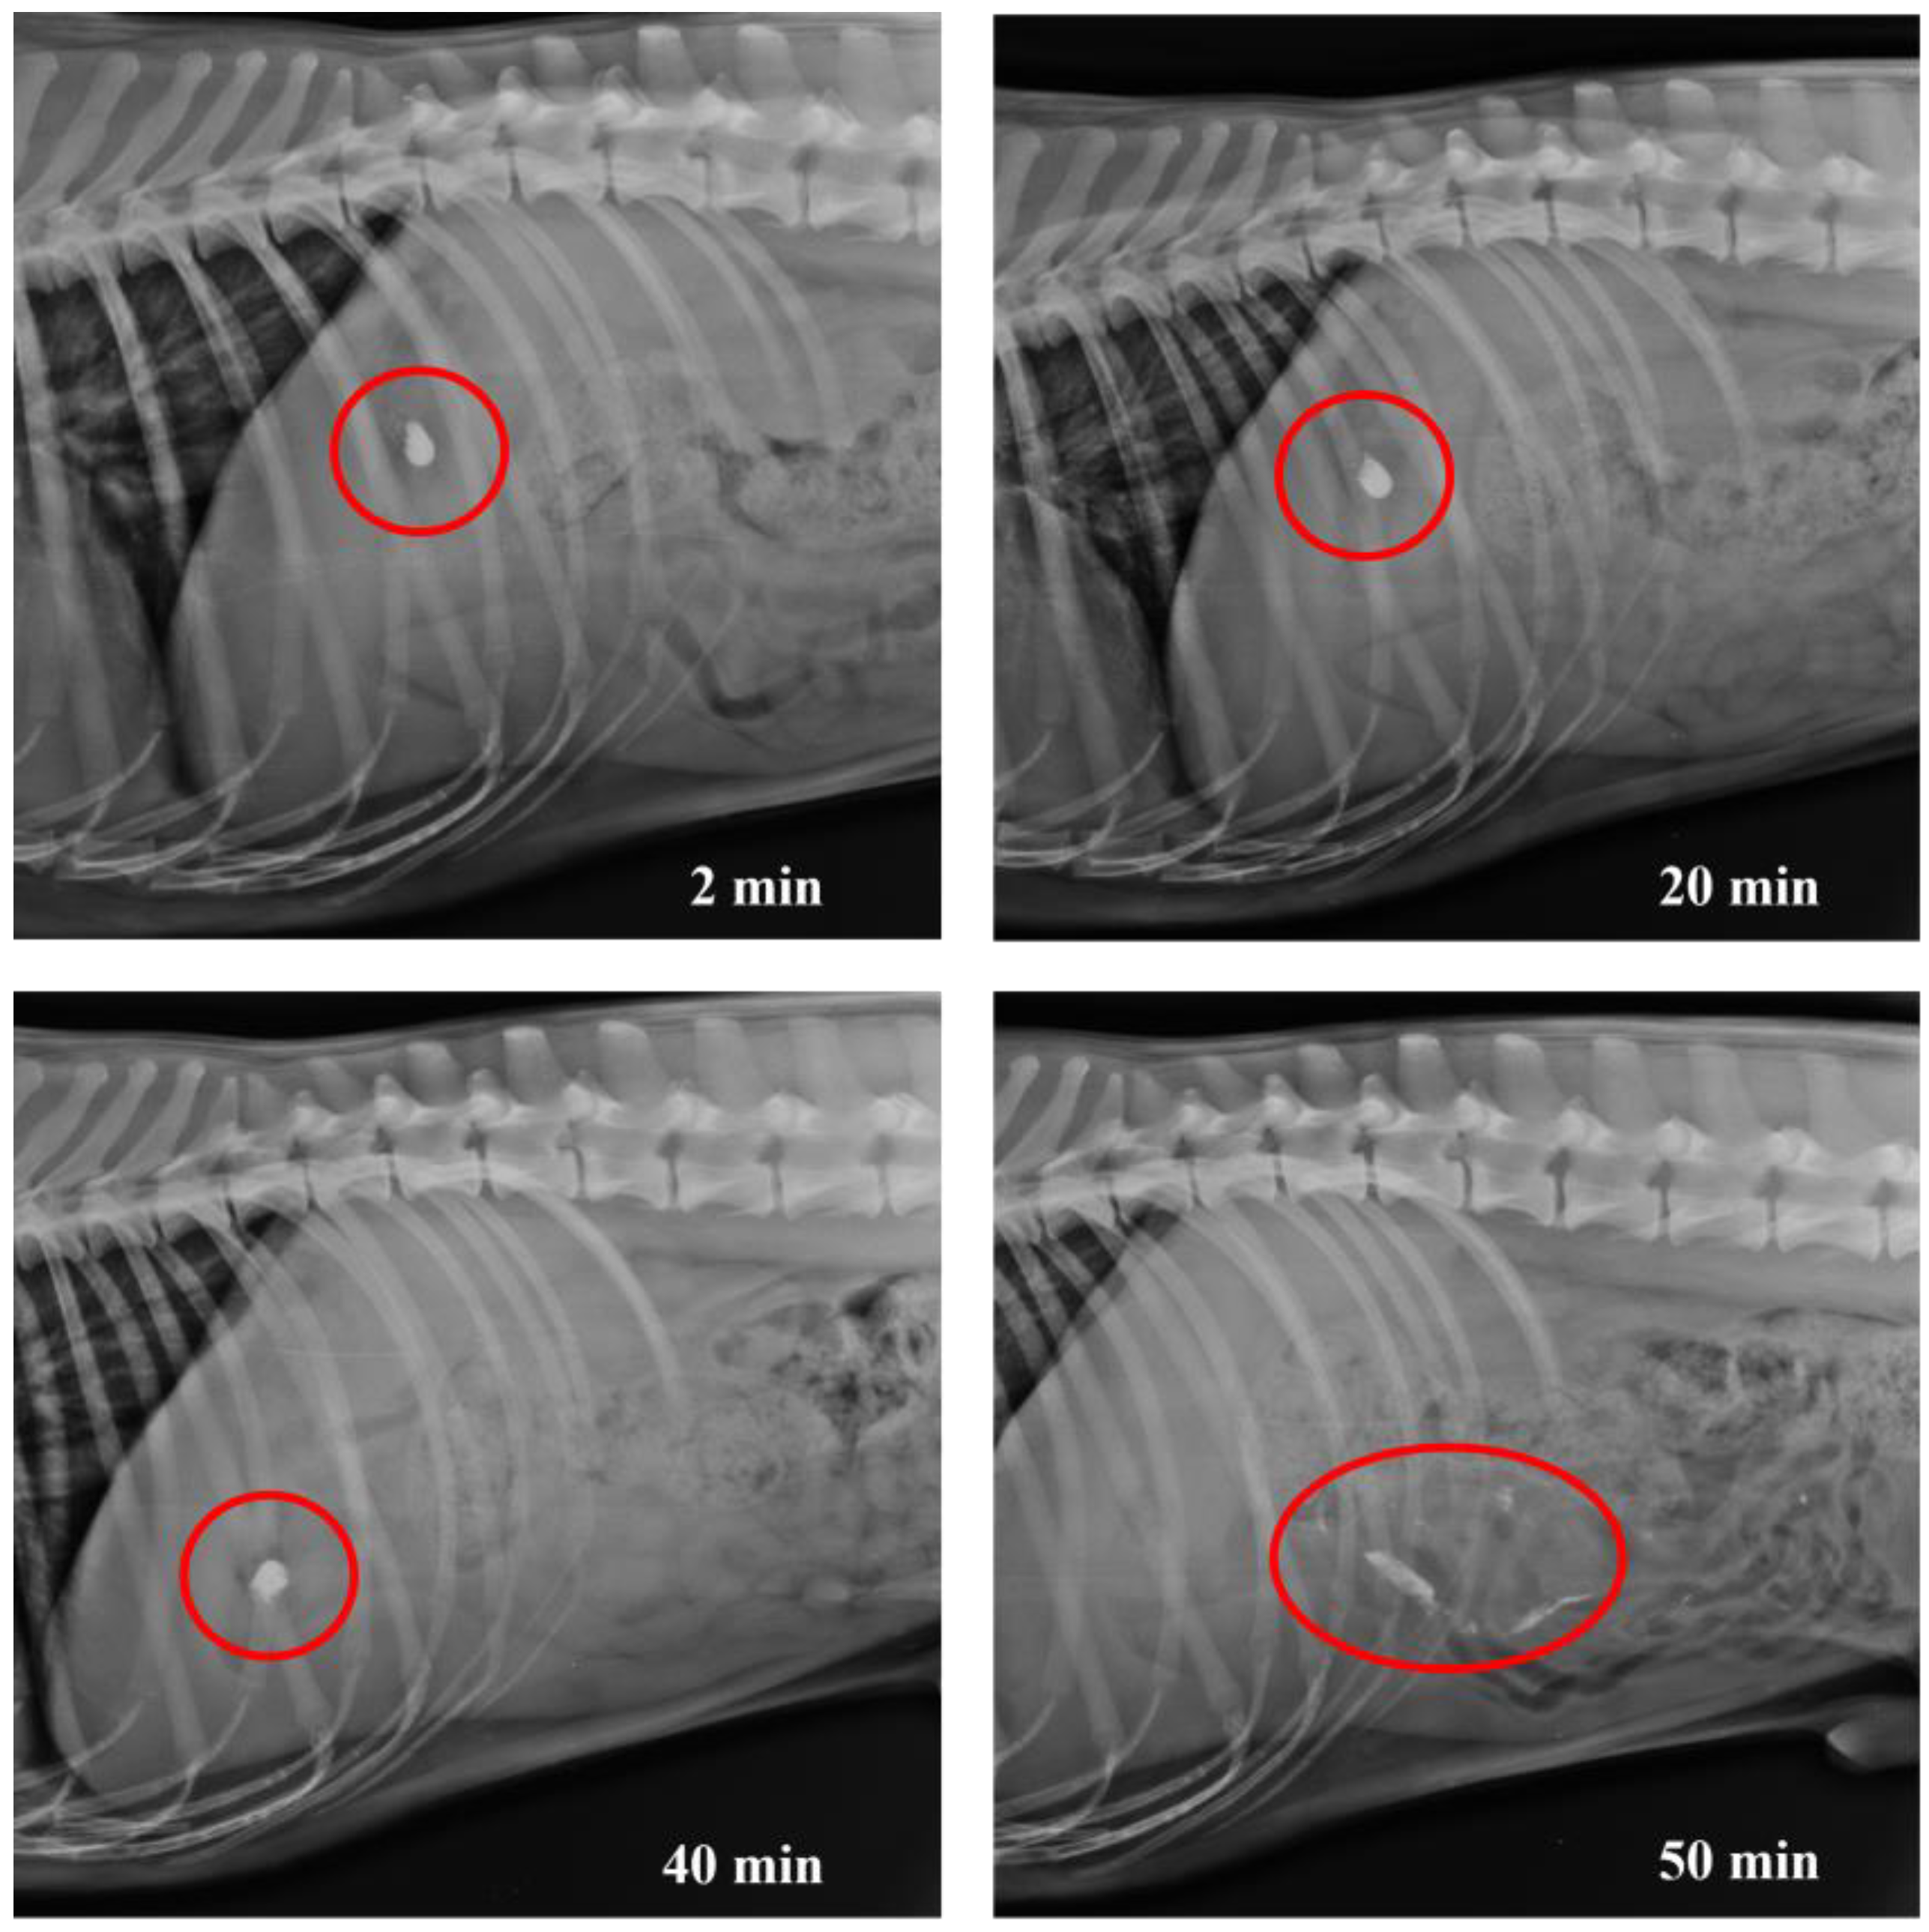

3.4. In Vivo Studies